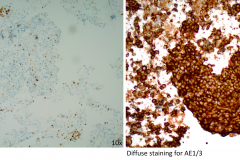

The cells of BSCC are positive for SCC markers p63 and p40.8, 9 Cytokeratin markers such as CK1, CK7 and CK14 are also positive in BSCC.10 In this case, AE1/3 was used to confirm epithelial differentiation11 along with p40 to confirm squamous differentiation (see figure 5). BSCC cells are negative for neuroendocrine markers synaptophysin and chromogranin, adenocarcinoma markers, and lymphoid markers.11, 12